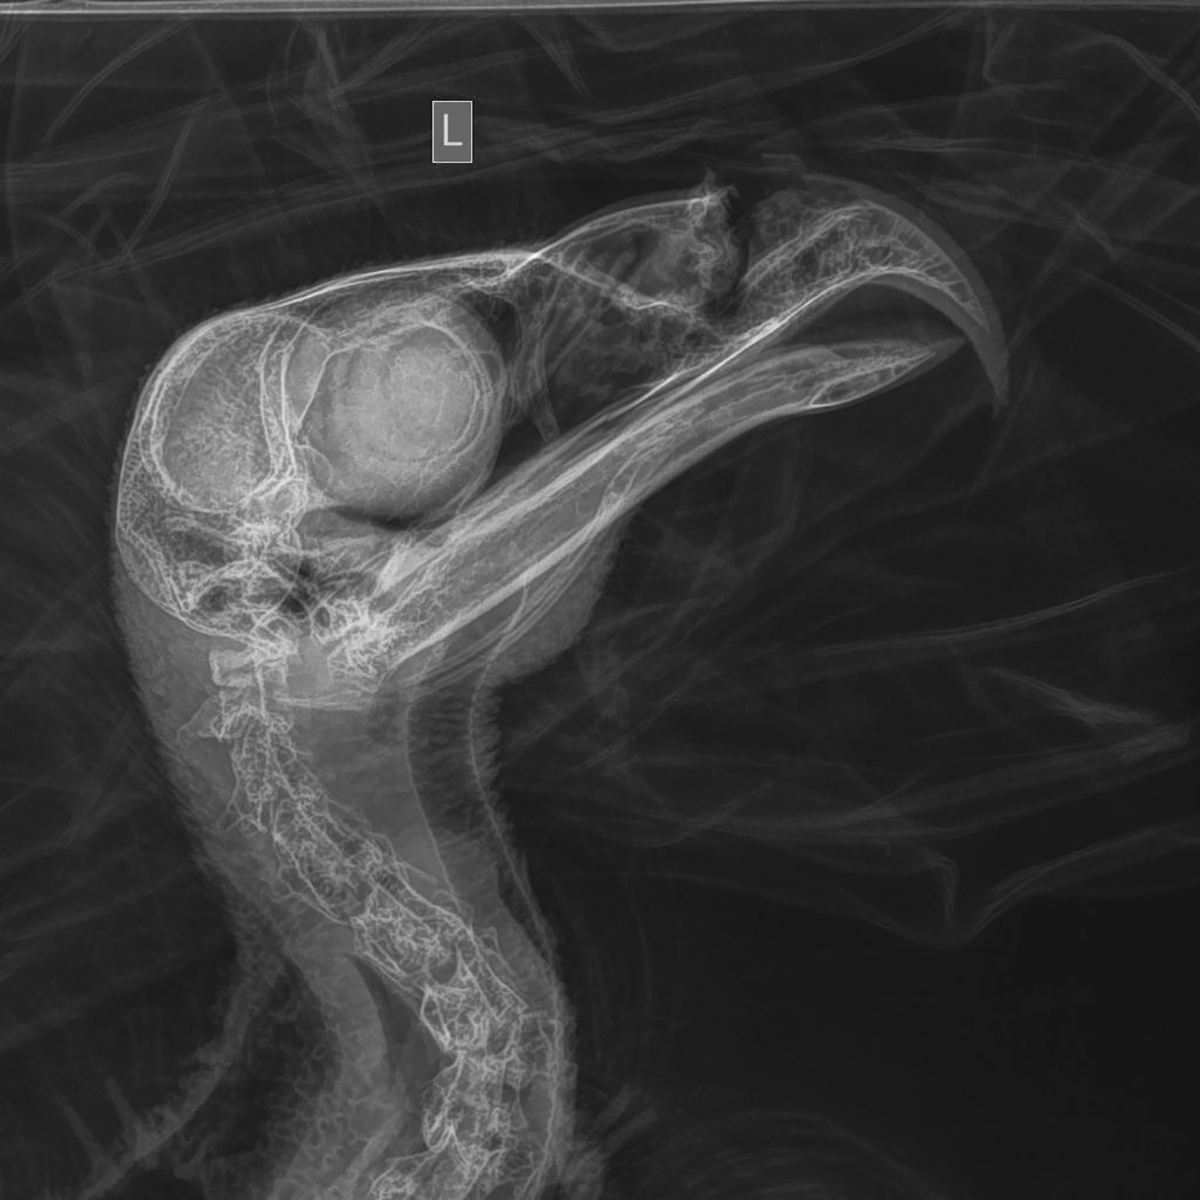

Roger Holloway, the sanctuary’s executive director, said the eagle’s upper beak was nearly split in half by the bullet. It also had an injured left wing and suffered from lead poisoning.

The eagle, designated No. 24-390 because it is the 390th injured bird treated at the sanctuary this year, has undergone three surgeries. Holloway said an operation last week was to further repair the severely damaged beak — a serious injury that would be life-ending if it doesn’t heal.

The good news: Suture sites from earlier surgeries are healing well, and so are jaw fractures caused by the force of the bullet, Holloway said. Another procedure is likely in early September.